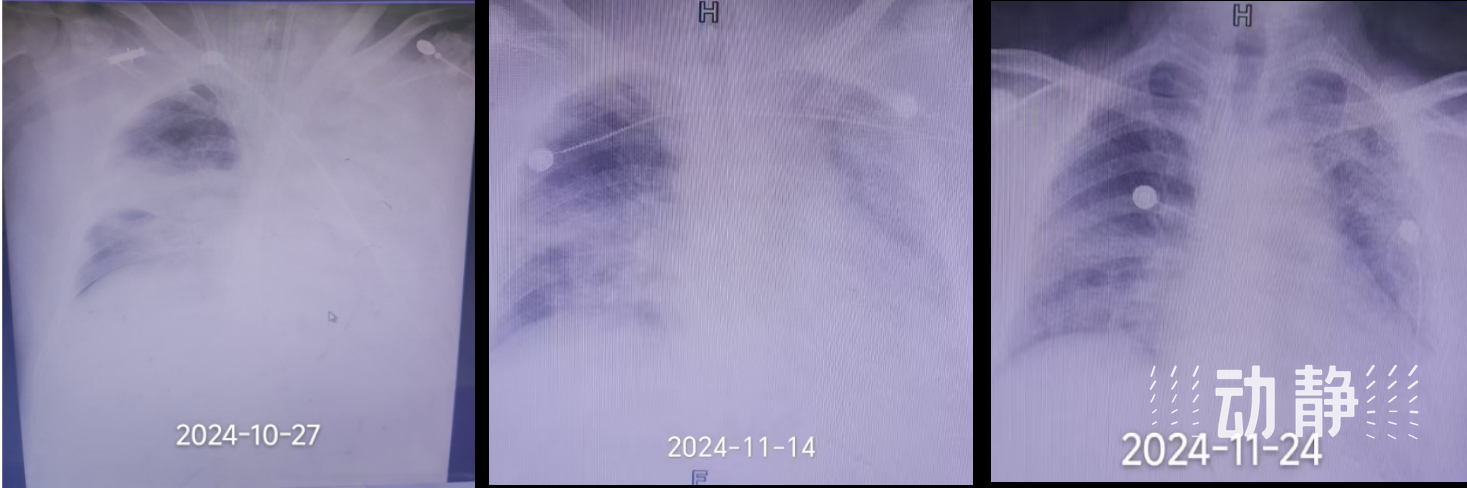

在ECMO的支持下,患者的氧合状况逐渐改善,为后续治疗赢得了宝贵的时间。重症医学科团队根据患者的具体情况,制定了抗病毒、俯卧位通气、器官保护、营养支持等一系列个体化、精准化的治疗方案。尽管在治疗初期,患者的胸部CT结果显示双肺实变仍然较重,但医护人员并未气馁,坚持与患者家属沟通病情,鼓励他们保持信心。

经过一段时间的治疗和观察,患者的肺部情况逐渐好转,“黑色”区域(代表肺部气体交换功能恢复的区域)逐渐增加。最终,在医护人员的精心治疗和护理下,患者成功撤离ECMO,并顺利康复出院。